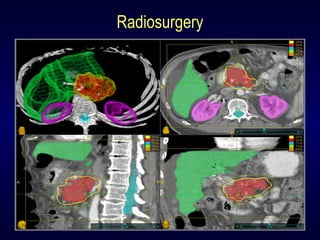

Radiosurgery

Modern SBRT Systems

Synchrony

TM

Fiducial based tracking along

with respiratory motion tracking